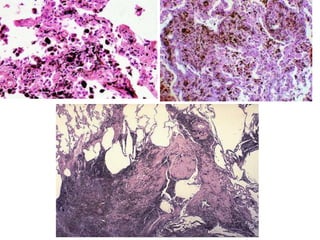

Microscopy

 Asbestos bodies: asbestos fibres coated with a film of proteins

rich in iron.

 Golden brown, fusiform or beaded rods.

 coating is thickest at ends - Dumbell shape

 form when macrophages phagocytose asbestos, iron derived

• Ferrugious bodies : other inorganic

particles/fibres coated with similar protein

iron complex

Pathologic features • Beginin lower lobes and sub pleura • Early stages – minimal fibrosis • Late stages- extensive fibrosis- destroys the architecture-dilated/cystic air spaces- honeycombed appeareance

Microscopy  Asbestos bodies:asbestos fibres coated with a film of proteins rich in iron.  Golden brown, fusiform or beaded rods.  coating is thickest at ends - Dumbell shape  form when macrophages phagocytose asbestos, iron derived from phagocyte ferritin.

• Ferrugious bodies: other inorganic particles/fibres coated with similar protein iron complex